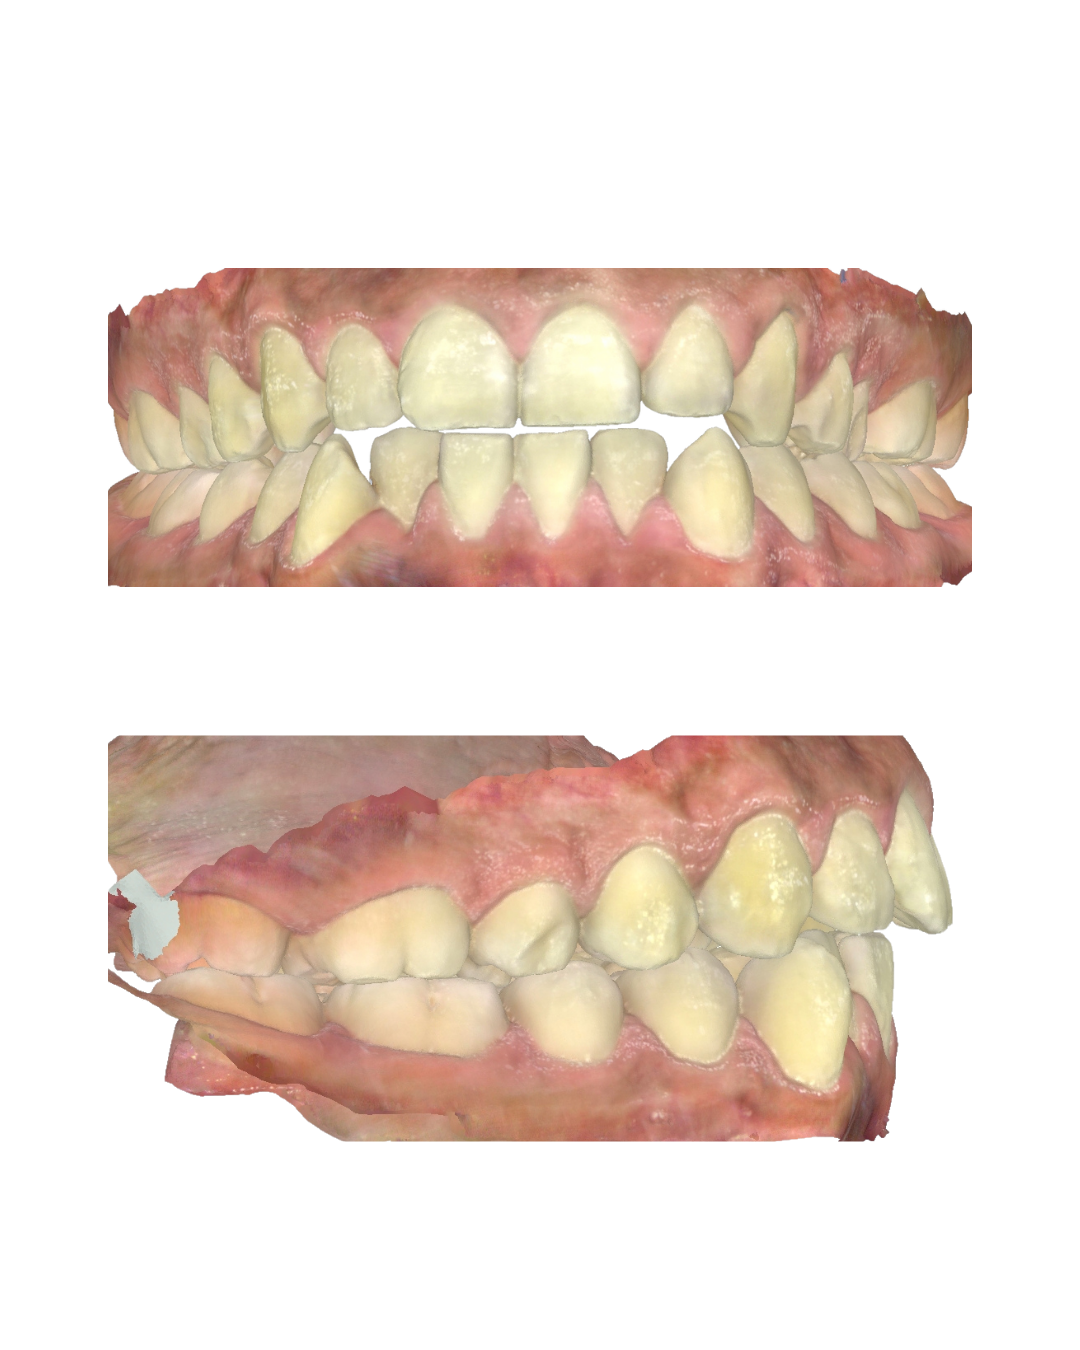

Subscribe — Full Library Free AccessIn this full case walkthrough video, you will see my go to mechanics for managing a crossbite with fixed appliances. You'll also see how I manage class I cases with generalised spacing to get a predictable results that patients love. In the video I share the reasons behind my decisions and below I'v...

In this video you'll see a full case walkthrough showing the mechanics I love to use to manage an anterior openbite (AOB) plus how I manage a posterior crossbite tendency affecting the upper second premolars. I'll explain the reasons behind every choice so you can apply good reasoning to your cases....